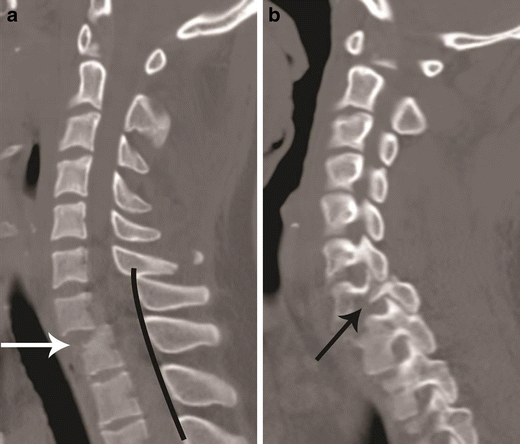

Bilateral versus unilateral facet joint dislocation. a Mid-sagittal CT image shows anterior translation of C5 over C6 by more than 50 % anteroposterior width of the C6, highly suggestive of bilateral facet joint dislocation, which was confirmed on parasagittal images (not shown). Large triangular bony fragment is noted at the posteroinferior corner of C5 (arrow) with diffuse loss of C5–C6 intervertebral disc space. b Mid sagittal CT image shows anterior translation of C4 over C5 by less than 50 % anteroposterior width of C5 (approximately 25 %), highly suggestive of unilateral facet joint dislocation, which was confirmed on parasagittal images (not shown). Small triangular bony fragment is noted at the anteroinferior corner of C4 (arrow) with loss of C4–C5 disc space. Disruption of spinolaminar line (black curved lines) at the level of anterolisthesis with anterior displacement of the same vertebra and lamina (C5 in a and C4 in b) is highly suggestive of hyperflexion injury. Presence of small avulsion fragments at the discovertebral junction with loss of intervertebral disc height is associated with disc injury, which needs further evaluation with MRI